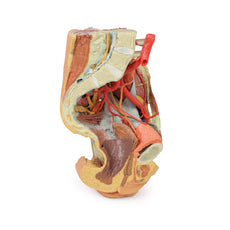

Following the course of the internal iliac artery deep to the undissected peritoneum, many of the major branches of its anterior and posterior divisions can be identified. The anterior division divides (deep to the peritoneum) into the superior vesical, obturator and obliterated umbilical artery. With a course parallel to the obturator artery, the obturator nerve can be seen running over obturator internus before entering the obturator canal together with the obturator vein (nerve, artery, vein in that order from superior to inferior).

Branches of the posterior division of the internal iliac artery, iliolumbar, and several lateral sacral arteries, can be seen arising from the posterior aspect of the internal iliac just below the sacral promontory. Its terminal branch, the superior gluteal, usually passes posteriorly between the lumbosacral trunk and S1 nerve, but this is hidden from view. The internal iliac vein and its tributaries - the obturator veins, uterine vein, vesical veins, etc. can be seen lying internal to the nerves and muscles. The large S1 and S2 roots and the smaller S3 nerve root can be seen emerging from the sacral foramina to pass laterally where it is joined by the lumbosacral trunk (L4 and l5 roots) which is not visible, to form the sciatic nerve which exits through the greater sciatic foramen to emerge on the posterior aspect in the gluteal region. In the pelvis as these roots pass laterally they are interdigitated between the fibres of piriformis muscle.

The right ureter can be clearly seen as it passes inferiorly on the posterior abdominal wall superficial to psoas muscle. It passes over the pelvic brim at the bifurcation of the common iliac artery to descend on the lateral wall of the pelvis before passing medially in the base of the broad ligament (hidden from view as the peritoneal folds that ‘drape’ over the uterine [Fallopian] tubes are still intact) to reach the lateral angles of the bladder. In the pelvis the viscera which lies most anteriorly is the bladder. Its thick wall and cavity is easily seen in this mid-sagittal cut. Indeed the ureteric orifice can be seen at the angle of the trigone of the bladder on its internal mucosal surface. The relations of the uterus to the vagina are clearly visible in the mid-sagittal section. Indeed the anterior and posterior fornices are clearly seen as is the os of the cervix. The round ligament of the uterus has been removed along with some peritoneum to display the structures in the lateral pelvic wall. The entire right Fallopian tube is identifiable as it passes from the lateral aspect of the body of the uterus to terminate as the fimbria which overhangs the right ovary which is still held in place by its mesovarium. The ovary is attached laterally to the pelvic brim by the suspensory ligament of the ovary (sometimes called the infundibulopelvic ligament) which contains its named artery and veins. The ligament of the ovary is clearly visible leading from the medial aspect of the ovary to the lateral surface of the uterus.

There are only small cut surfaces of the rectum (visible as little islands of mucosa) visible on the sagittal cut surface suggesting that it is slightly off the midline plane. Some pararectal lymph nodes (coloured pale green) can be seen close to these islands of rectal mucosa. On the anterior aspect of the 3D print the inguinal ligament has been retained and deep to it the femoral artery, vein and nerve pass to the anterior compartment of the thigh.

Following the course of the internal iliac artery deep to the undissected peritoneum, many of the major branches of its anterior and posterior divisions can be identified. The anterior division divides (deep to the peritoneum) into the superior vesical, obturator and obliterated umbilical artery. With a course parallel to the obturator artery, the obturator nerve can be seen running over obturator internus before entering the obturator canal together with the obturator vein (nerve, artery, vein in that order from superior to inferior).

Branches of the posterior division of the internal iliac artery, iliolumbar, and several lateral sacral arteries, can be seen arising from the posterior aspect of the internal iliac just below the sacral promontory. Its terminal branch, the superior gluteal, usually passes posteriorly between the lumbosacral trunk and S1 nerve, but this is hidden from view. The internal iliac vein and its tributaries - the obturator veins, uterine vein, vesical veins, etc. can be seen lying internal to the nerves and muscles. The large S1 and S2 roots and the smaller S3 nerve root can be seen emerging from the sacral foramina to pass laterally where it is joined by the lumbosacral trunk (L4 and l5 roots) which is not visible, to form the sciatic nerve which exits through the greater sciatic foramen to emerge on the posterior aspect in the gluteal region. In the pelvis as these roots pass laterally they are interdigitated between the fibres of piriformis muscle.

The right ureter can be clearly seen as it passes inferiorly on the posterior abdominal wall superficial to psoas muscle. It passes over the pelvic brim at the bifurcation of the common iliac artery to descend on the lateral wall of the pelvis before passing medially in the base of the broad ligament (hidden from view as the peritoneal folds that ‘drape’ over the uterine [Fallopian] tubes are still intact) to reach the lateral angles of the bladder. In the pelvis the viscera which lies most anteriorly is the bladder. Its thick wall and cavity is easily seen in this mid-sagittal cut. Indeed the ureteric orifice can be seen at the angle of the trigone of the bladder on its internal mucosal surface. The relations of the uterus to the vagina are clearly visible in the mid-sagittal section. Indeed the anterior and posterior fornices are clearly seen as is the os of the cervix. The round ligament of the uterus has been removed along with some peritoneum to display the structures in the lateral pelvic wall. The entire right Fallopian tube is identifiable as it passes from the lateral aspect of the body of the uterus to terminate as the fimbria which overhangs the right ovary which is still held in place by its mesovarium. The ovary is attached laterally to the pelvic brim by the suspensory ligament of the ovary (sometimes called the infundibulopelvic ligament) which contains its named artery and veins. The ligament of the ovary is clearly visible leading from the medial aspect of the ovary to the lateral surface of the uterus.

There are only small cut surfaces of the rectum (visible as little islands of mucosa) visible on the sagittal cut surface suggesting that it is slightly off the midline plane. Some pararectal lymph nodes (coloured pale green) can be seen close to these islands of rectal mucosa. On the anterior aspect of the 3D print the inguinal ligament has been retained and deep to it the femoral artery, vein and nerve pass to the anterior compartment of the thigh.